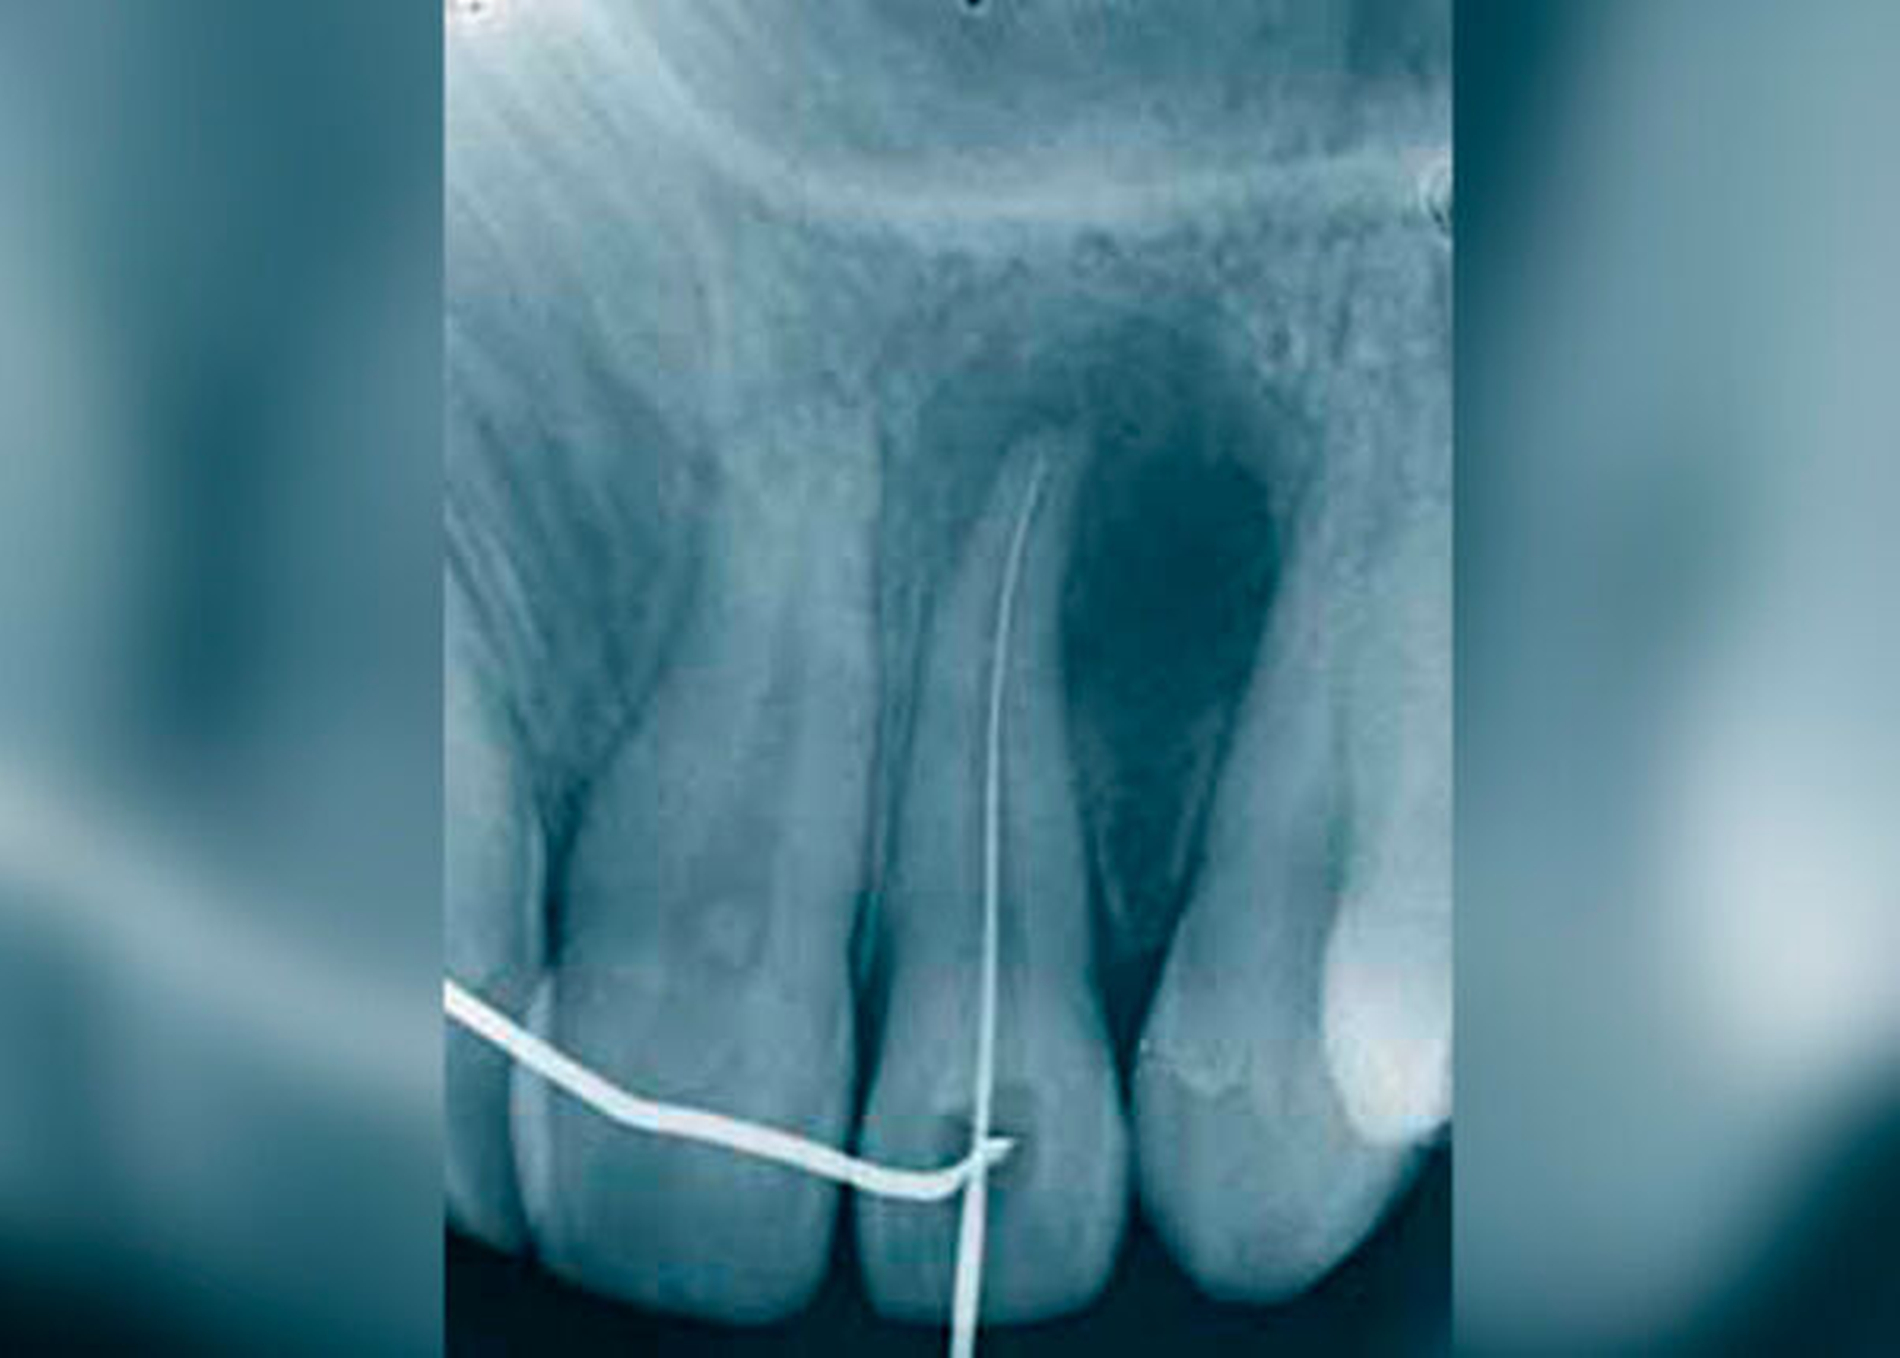

Die GZ wurde auch der parodontalen Zyste gegenübergestellt. Während letztere zwischen den Wurzeln sämtlicher Zähne entstehen kann, erscheint die GZ typischerweise nur zwischen dem lateralen Schneidezahn und dem Eckzahn, dort wo sich Prämaxilla und Maxilla vereinen. Es wurde Wert darauf gelegt, dass die Zyste zwischen parodontal und pulpal gesunden Zähnen vorkommt und somit ein Zweifel an ihrem fissuralen Ursprung ausgeschlossen ist. Die GZ verdrängt die Wurzeln des lateralen Incisivus und des Eckzahns, was als erstes klinisches Zeichen beschrieben wird. Später kann es zu einer Vorwölbung der vestibulären Schleimhaut kommen, oft assoziiert mit einem Druckgefühl (Abb. 1 bis 5).

Ein odontogener Ursprung der bis dahin als GZ bezeichneten Zysten wurde nun als wahrscheinlicher angesehen. 63 Fälle von GZ wurden in einer retrospektiven Studie analysiert [Christ, 1970]. Die Diagnose GZ wurde nur zugelassen, wenn ein Röntgenbild vorhanden war, die benachbarten Zähne vital waren und histologisches Material vorlag. Von den 63 untersuchten Fällen erfüllten nur sechs alle diese Kriterien, meist fehlten die histologischen Unterlagen.

Die klinische und pathohistologische Evidenz spricht überzeugend dafür, dass Zysten im „Globulomaxillären Bereich“ radikuläre Zysten, laterale Parodontalzysten, odontogene Keratozysten [Christ, 1970], kalzifizierende odontogene Zysten, adenomatoide odontogene Tumore [Rosenberg & Cruz, 1963; Giansanti et al., 1970; Khan et al., 1977], odontogene Myxome [Rud, 1964; Taicher & Azaz, 1977], Ameloblastome [Aisenberg & Inman, 1960], zentrale Riesenzellgranulome oder hämorrhagische Knochenzysten [Peters & Wassow, 1968] sind (Abb. 6 bis 13).

Auch die Möglichkeiten von invaginierten Zähne [Galindo-Moreno et al., 2003] oder von apikalen Infektionen, die beim Foramen caecum oberer lateraler Inzisivi ihren Ursprung genommen haben, sollten in die Differentialdiagnose miteinbezogen werden. Zahninvaginationen kommunizieren häufig mit der Pulpa, was früher oder später zur Pulpanekrose und zur Parodontitis apicalis führen und eine GZ vortäuschen kann [Galindo-Moreno et al., 2003]. Eine Entstehungstheorie aus einer verkümmerten Zahnanlage im „Globulomaxillären Bereich“ klingt zwar verlockend, wurde aber in der Literatur bis heute nicht ausreichend untersucht.